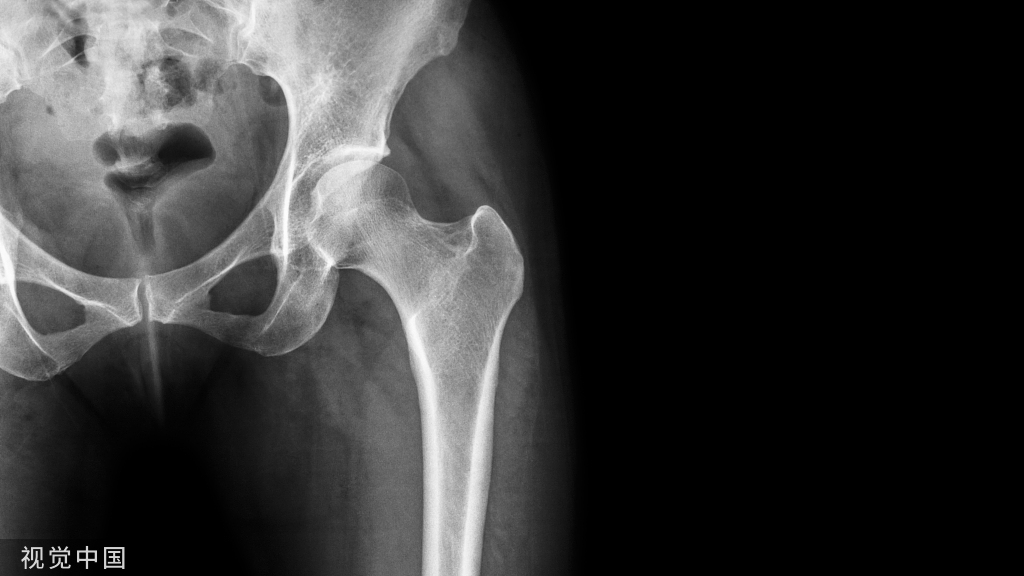

辅助检查

• X—RAY 踝关节正侧位(必要时应加照踝穴位)

• B超

• MRI

应力位片